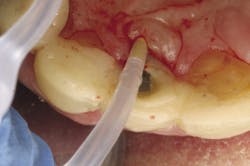

The term peri-implant mucositis describes a reversible inflammatory reaction in the mucosa adjacent to an implant,9 a term that has become known as implant gingivitis. Typical treatment involves quadrant scaling and root planing with implant-friendly armamentarium. The literature also has shown that mechanical debridement in conjunction with systemic and/or local antibiotic placement has increased the efficacy of this type of treatment10, but it can obviously be associated with higher treatment costs (Fig. 2). Studies show that the prevalence of peri-implant mucositis can be as high as 50% to 80% of implants in function.11 Peri-implantitis has been defined as an inflammatory process that affects the tissues around an osseointegrated implant in function and, like periodontitis, results in loss of supporting bone.